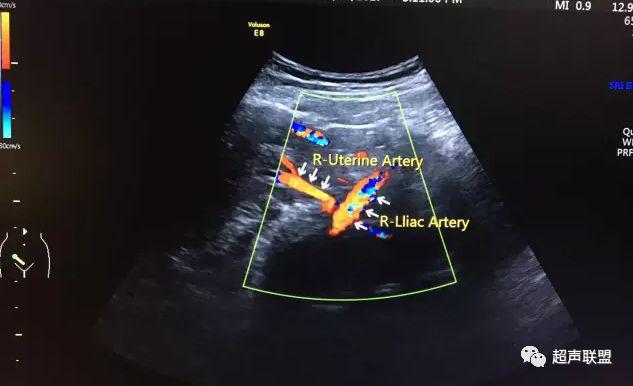

5 子宫动脉血流测定

正常妊娠时血流速度增加,血流阻力下降。缺氧早期的血流再分配,子宫动脉血流RI、PI值增加,阻力指数(RI)>0.57,子宫动脉血流频谱出现切迹。

3、子宫动脉标准:孕26或27周后,子宫动脉S/D>2.7,(RI)>0.57,有舒张早期切迹;

图7 正常中孕期子宫动脉频谱

图8 胎儿宫内缺氧,子宫动脉舒张早期可见切迹